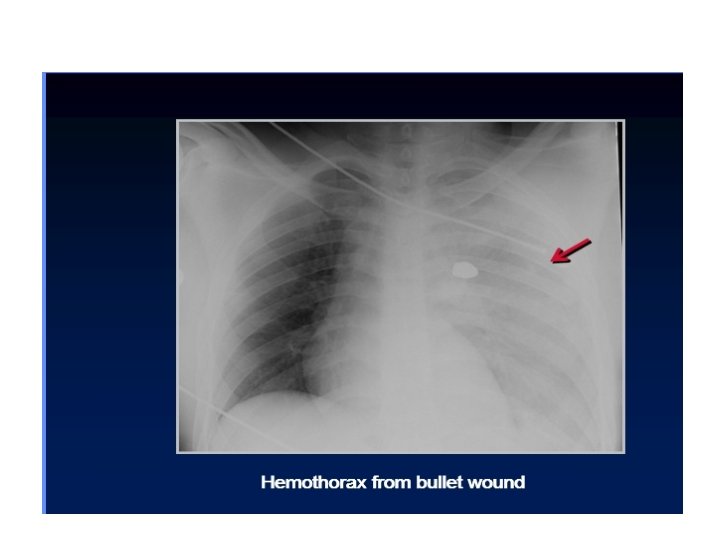

Chest trauma